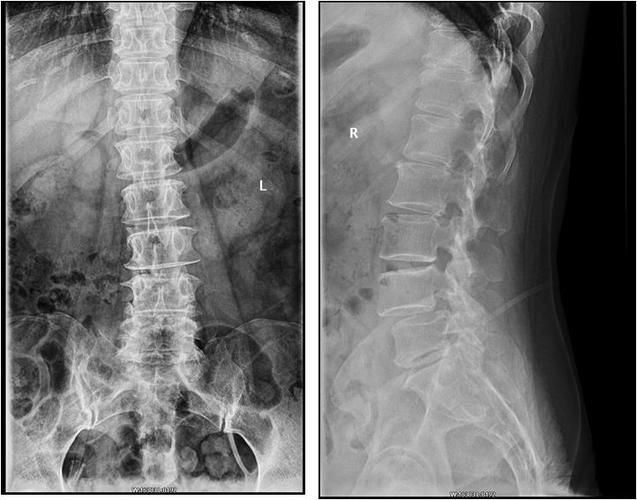

求会看x光片的大师们给看看这腰椎片有什么问题

专科检查:腰椎生理弯曲存在,腰椎活动度受限;腰4-5棘突及棘突旁压痛

下面这张x光片可以表示脊椎侧弯,从后面看腰椎棘突的连线像写一个「c